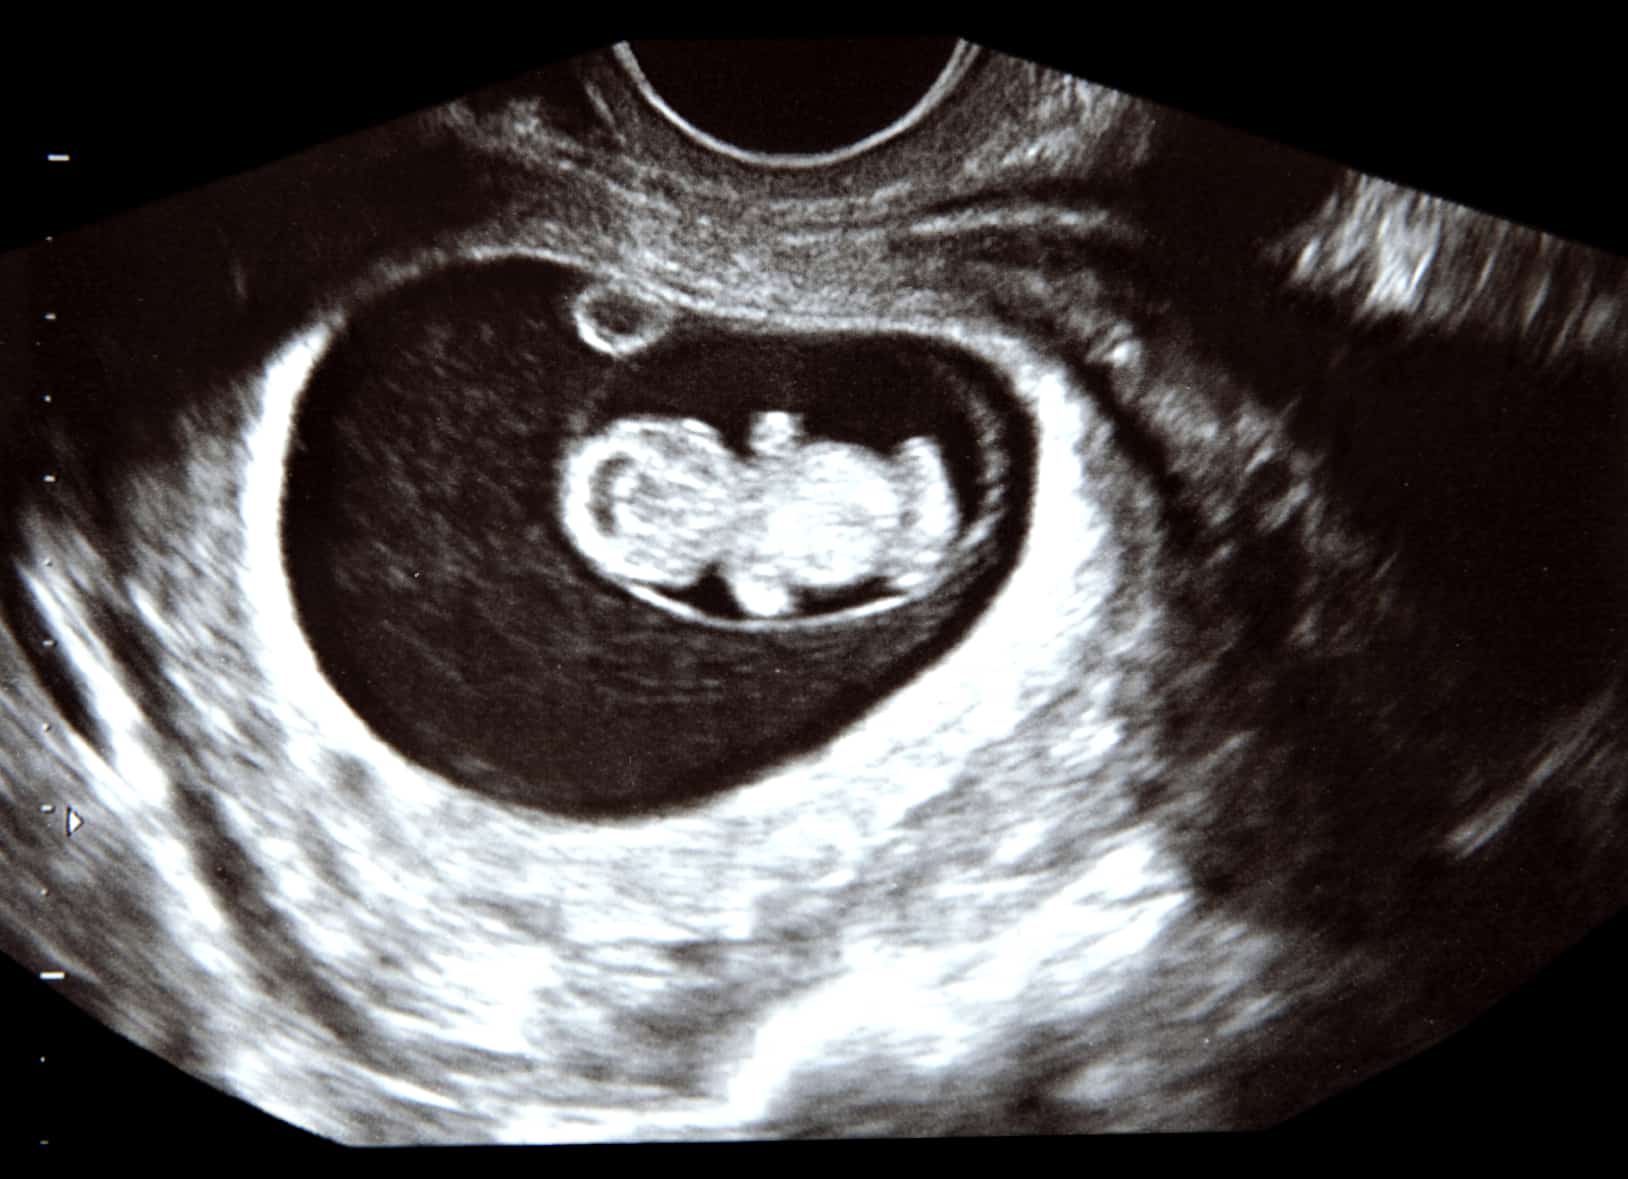

Image 13 Week Fetus

Image 13 Week Fetus

Gallery Image for Image 13 Week Fetus

Ultrasound Pictures 8 Weeks Pregnant Vrogue co